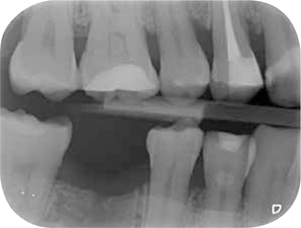

Röntgenonderzoek

Röntgenologisch onderzoek laat meerdere problemen zien. Onder andere een forse zwarting apicaal van element 12 met het beeld passend bij periapicale problematiek en een verleden van apicale chirurgie (afbeelding 8-12 ).

Afb. 9-10

Solo-opnamen van het 1e en 3e kwadrant.